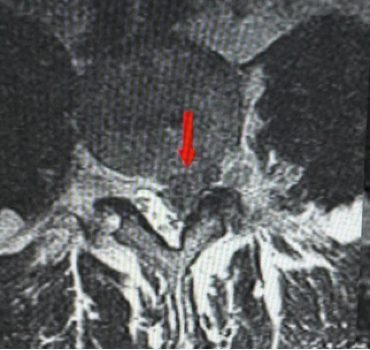

MRI scans – the most accurate test for visualizing discs and nerves

The gold standard imaging for disc prolapse is MRI:

• MRI clearly shows the disc, its position, the degree of prolapse, and the exact nerve or spinal cord being compressed

• It identifies the level and type of prolapse — contained, extruded, or sequestered

• Essential for surgical planning and confirming the diagnosis